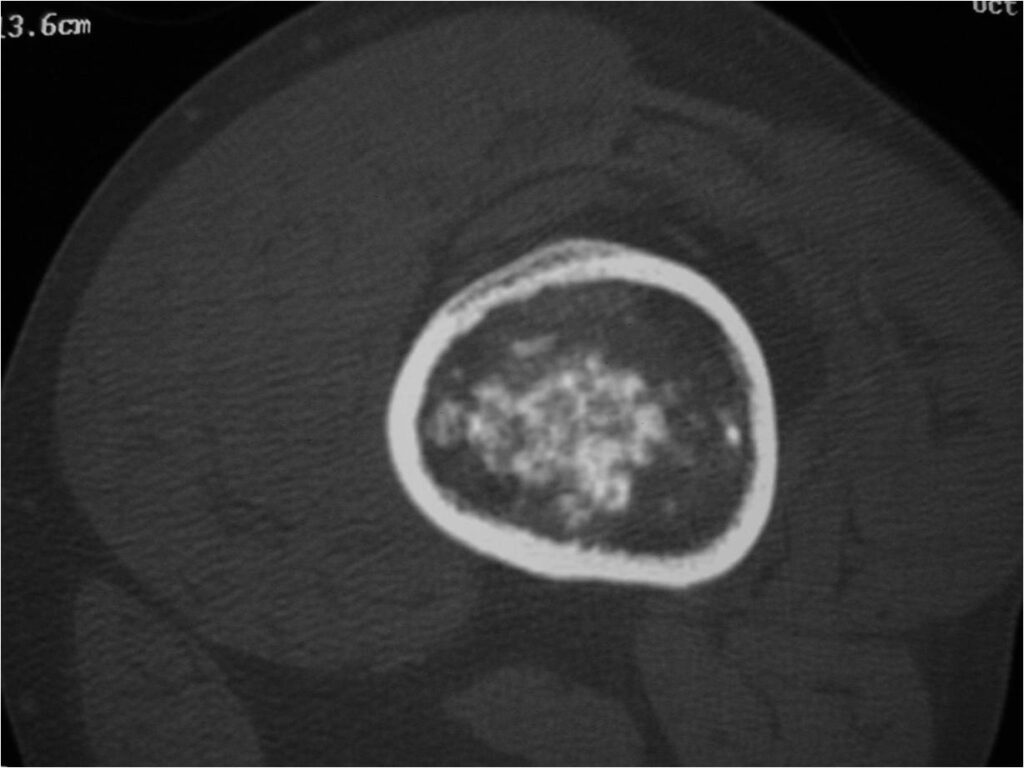

- Localized, radiolucent defect usually with punctate calcifications

- Calcifications are typical but not always present

- Matrix may demonstrate various degrees of calcification

- Calcifications are stippled, punctate, popcorn like calcifications and “Ring and Arc” calcifications

Plain X-Ray:

- Geographic lytic lesion

- Central often metaphyseal in long bones

- Expansile remodeling with thinned cortex

- Chondroid matrix with calcifications in majority of tumors

- There should never be any cortical destruction nor a soft tissue component. If this exists then the tumor must be a chondrosarcoma.

- Endosteal scalloping and cortical expansion is acceptable for phalangeal tumors. In most benign long bone cartilage tumors there is minimal endosteal scalloping but there should be no cortical expansion nor thickening. There should be no cortical destruction and no soft tissue component associated with an enchondroma. Cortical destruction, periosteal thickening, cortical expansion and a soft tissue component indicates a chondrosarcoma of the long bone.

- Features consistent with chondrosarcoma

- Pain attributable to lesion

- Age greater than 50

- Cortical destruction and a soft tissue mass

- Periosteal reaction and thickening

- Endosteal erosion>2/3 cortical thickness on a CT scan

- Size greater than 5 cm